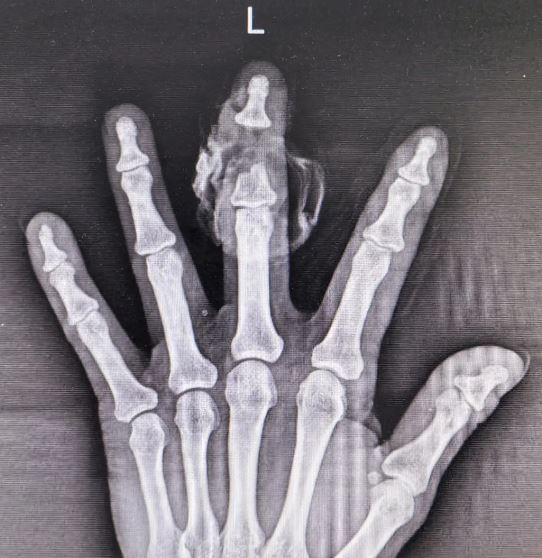

接診后,我院醫(yī)學(xué)美容中心副主任張治家博士立即為其完善影像與專科檢查,確診:左手第3中節(jié)指骨中遠(yuǎn)段骨質(zhì)缺如、左手中指不全離斷、左手食、中指開放性損傷、皮膚軟組織缺損。

臨床中此類創(chuàng)傷處理難度極大:中節(jié)指骨缺失造成手指骨性支撐中斷,軟組織破損污染嚴(yán)重。常規(guī)處理多需截指清創(chuàng),這不僅會(huì)造成手部殘缺畸形,還會(huì)嚴(yán)重影響抓握、勞作等日?;A(chǔ)功能,給患者后續(xù)生活、心理及就業(yè)帶來(lái)沉重打擊。

考慮到患者手指并未完全離斷,仍保留部分軟組織相連與血運(yùn)基礎(chǔ),為最大限度保留手指完整性,且減少患者二次創(chuàng)傷的痛苦及經(jīng)濟(jì)壓力,張治家主任手術(shù)團(tuán)隊(duì)反復(fù)研判傷情,結(jié)合患者骨骼缺損范圍、軟組織存活條件及個(gè)體身體等因素,綜合考慮,最終制定修復(fù)重建方案:決定行皮膚傷口切除性清創(chuàng)術(shù)、左手中指遠(yuǎn)端指間關(guān)節(jié)剔骨成形內(nèi)固定術(shù)、甲成形術(shù)、旋轉(zhuǎn)皮瓣移植術(shù)、殘端皮膚修整術(shù)。

術(shù)中,張治家主任細(xì)致徹底清創(chuàng),清除污染、壞死骨質(zhì)及軟組織。根據(jù)手指的正常形態(tài),精心雕琢打磨修整指骨殘端及關(guān)節(jié)面,模擬正常手指生理結(jié)構(gòu)完成骨骼對(duì)接,使用可吸收釘板牢固固定。同時(shí),盡可能多地保留患者健康碎骨填塞間隙,最大限度保留手指長(zhǎng)度,增加骨結(jié)構(gòu)的穩(wěn)定性,并充分保護(hù)甲床及甲根組織,修整固定甲床組織,恢復(fù)手指指甲外形。